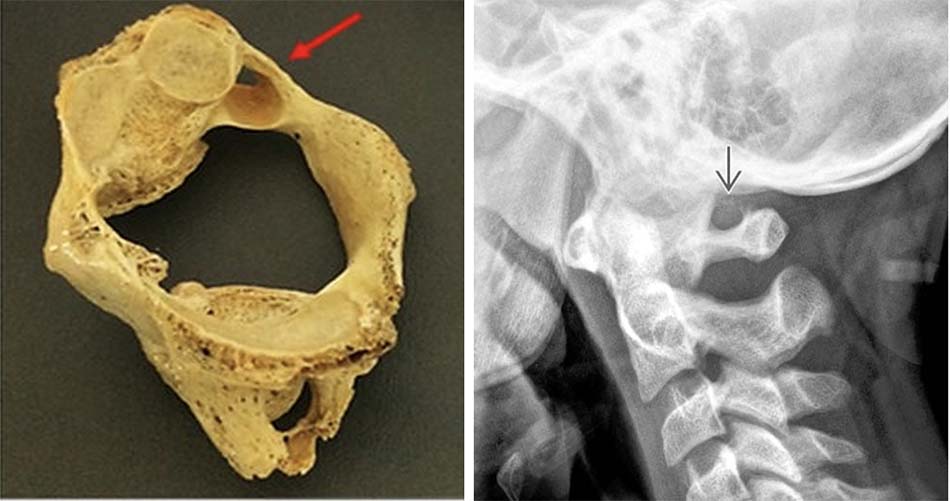

Spitzer và cộng sự đã mô tả mất vững khớp chẩm – đội và thiểu sản đốt đội trong hội chứng Down [12]. Phân loại dị tật mỏm nha chia ra:

- Không có mỏm nha: là dị tật mỏm nha không phát triển, trên Xquang thường quy không có mỏm nha.

Hình 1.35. Hình ảnh Xquang không có mỏm nha. - Thiểu sản mỏm nha: mỏm nha phát triển bán phần, có hình dạng khác nhau có thể là 1 mẩu ngắn hoặc có thể có kích thước gần như bình thường.

Hình 1.36. Thiểu sản mỏm nha trên Xquang - Khớp giả mỏm nha: Mỏm nha được chia làm 2 đoạn, trong đó có một đoạn tách rời.

Hình 1.37. Mất vững C1-C2, khớp giả mỏm nha trên Xquang thường quy

Hình 1.38. Khớp giả mỏm nha trên cắt lớp vi tính (hội chứng Down).

Trong khớp giả mỏm nha, giữa mỏm nha và thân đốt trục có hình ảnh giống một khe khớp nhìn trên phim xquang. Phân biệt hình ảnh khớp giả này với khớp bán động sụn trung tâm thường gặp ở trẻ dưới 5 tuổi. Vì vậy, đối với trẻ dưới 5 tuổi, chẩn đoán khớp giả mỏm nha được xác định bằng sự di lệch của mỏm nha và thân đốt trục trên hình ảnh phim Xquang động.

Ở người lớn, chẩn đoán khớp giả mỏm nha có thể qua Xquang với hình ảnh khe khớp giữa mỏm nha và thân đốt trục. Khe khớp ở khớp giả mỏm nha giữa mảnh tự do và đốt trục thường nằm cao hơn vị trí của diện khớp đội – trục bên và có đường viền nhẵn. Mảnh rời thường có kích thước bằng 1/2 kích thước mỏm nha bình thường, hình tròn hoặc bầu dục, vỏ xương dày.

Khớp giả do chấn thương đường khe khớp hẹp, bất thường và đường gãy thường kéo dài đến thân đốt đội, dưới diện khớp đội – trục bên. Mảnh rời mỏm nha liền với phần trước của đốt đội và di chuyển theo vận động ngửa, gập hoặc nghiêng cổ hai bên.